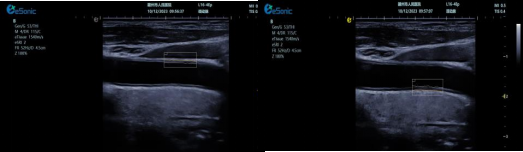

)其他超声技术集成

银河官网超声系统融合 e IMT 内中膜自动测量、超高频高分辨线阵探头、TCCD、心脏彩色多普勒超声等高端台式彩超功能,数据处理能力强,大幅提升人体组织显示分辨率。优势体现为:

? e IMT 内中膜自动测量可自动检测厚度,智能匹配与包络,自动设置取样框,实时或冻结状态下均可测量前壁及后壁厚度,提供多组数值,减少人工误差,便捷准确。

image.png

超高频探头能清晰显示颈动脉内中膜及斑块细节,辅助判断斑块易损性。

? TCCD 技术可评估脑动脉硬化与狭窄程度,全面预警脑卒中风险。

? 心脏彩色多普勒超声有助于判断脑卒中心源性风险因素,完善诊断信息。